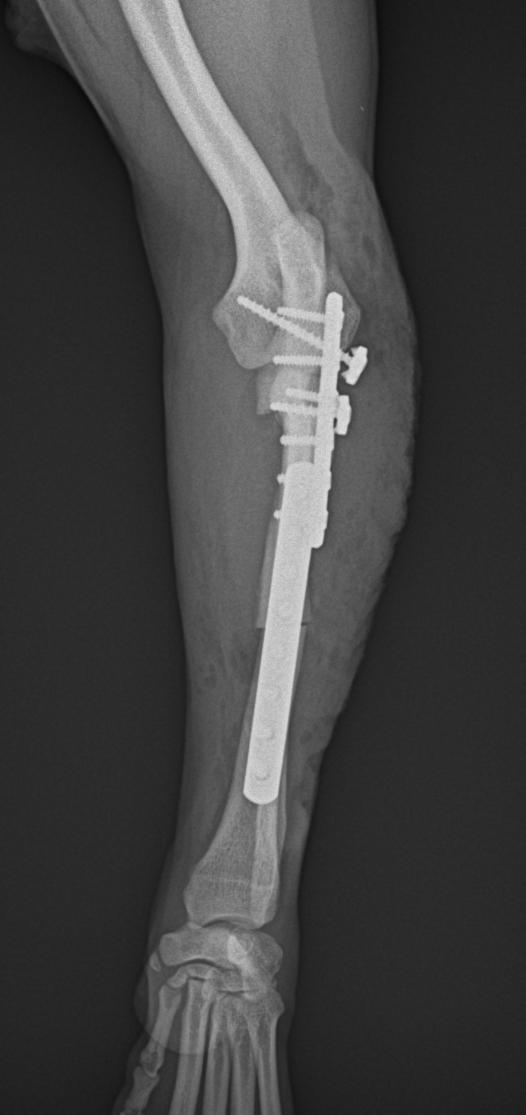

2歳の柴犬ちゃんが、生まれてすぐに痛めた肘に徐々に痛みが出てきたとのことで、主治医から診察と必要があれば手術をして欲しいと連絡がありました。CTでは橈骨頭が外側に脱臼して変位していました。また回転性の変形を伴っています。同時に尺骨にも湾曲が認められています。このような変形矯正には3Dプリンターで模擬手術を行いあらかじめシミュレーション手術をしておくと時間の短縮と正確な変形矯正が可能となります。このようなテクノロジーを動物医療にもどんどん取り入れていきたいと思います。また、骨きり部位にはPRFと自家海綿骨移植を行い治癒促進を期待します。